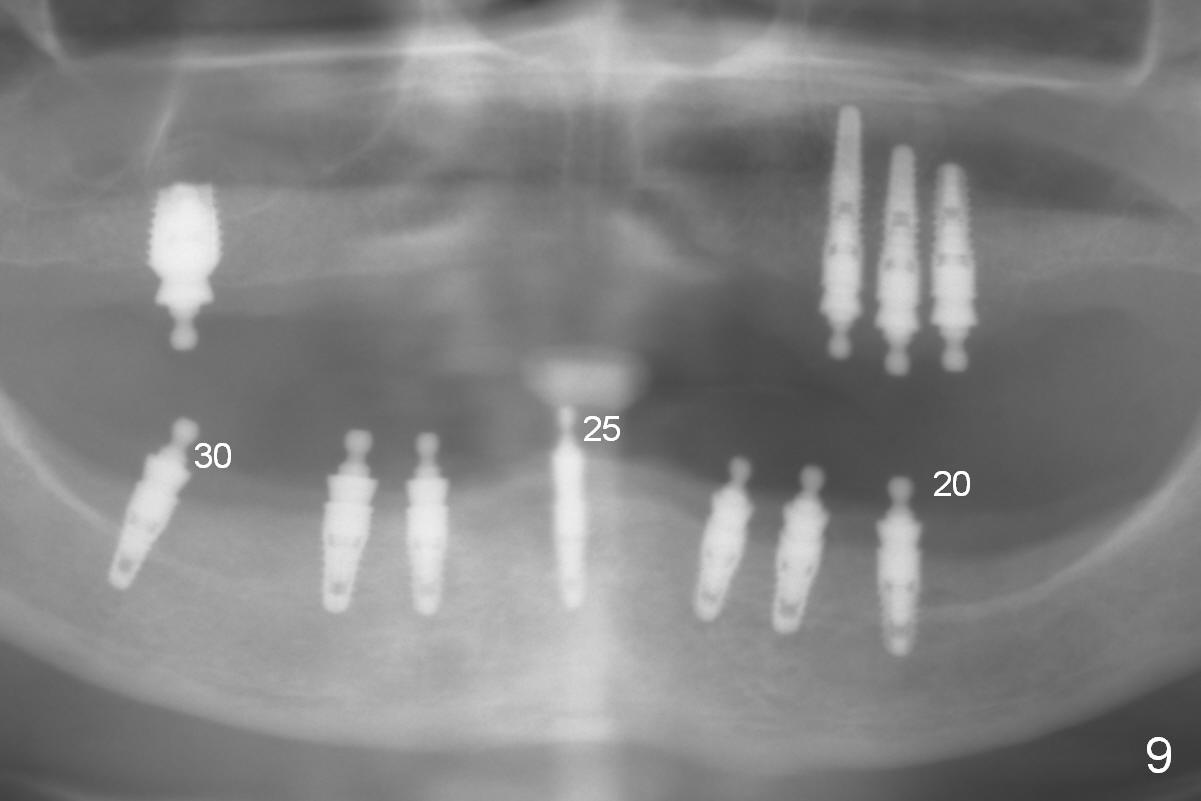

In the 2nd stage, three implants are placed at #20,25 and 30 (Fig.9).

At the site of #30, the lingual plate perforates in the early stage of osteotomy (Fig.1 red arrow). As indicated by the thick lingual plate, the osteotomy turns out to be difficult. The trajectory is corrected immediately (Fig.2 red) and with control so that the Inferior Alveolar Canal (brown circle) will be not be violated. The perforation is repaired with Osteogen plug (Fig.3 white) and nearby autogenous bone (red circles) before placement of a 3.8x8 mm implant (green).

At the site of #20, osteotomy for the same implant is finished without sign of nerve injury or lingual plate perforation. To place the implant a little deeper, a 2 mm drill is used to deeper for another 2 mm. The latter also turns out to be hard. When it is done, perforation occurs, noticed first by the patient (Fig.4). The perforation is fixed with Osteogen plug (Fig.5 white area), while the implant is placed at the crestal level as planned.

It appears that a longer implant (3.8x10 mm) can be placed at #25. The effort to deepen the osteotomy beyond the planned level fails. It feels that the drill is dull. The patient does not like vibration associated with the further osteotomy. The drill must be contacting the extremely dense lingual plate next to mental tubercles (Fig.6). Finally a 3.8x8 mm implant (Fig.7) is placed deeper than planned (Fig.8). There is no sublingual edema or hematoma postop.